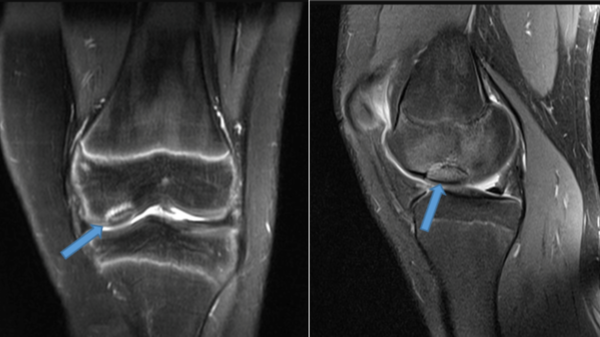

L’articolazione più frequentemente colpita dall’osteocondrite dissecante è il ginocchio, la sede più comune è il condilo femorale mediale, mentre le lesioni sul condilo laterale sono quelle che più spesso si associano ad instabilità rotulea.

La radiografia può mettere in evidenza le alterazioni dell’osso o la presenza di un frammento instabile o libero nell’articolazione. Tuttavia, non è in grado di determinare la stabilità del frammento osseo né di valutare le dimensioni della lesione.

La risonanza magnetica (RM) è utile per valutare le dimensioni, la stabilità della lesione e la presenza di corpi liberi intrarticolari. È l’esame più affidabile in quanto altamente specifico e sensibile e indispensabile per una diagnosi certa; utile per controllare gli effetti del trattamento.